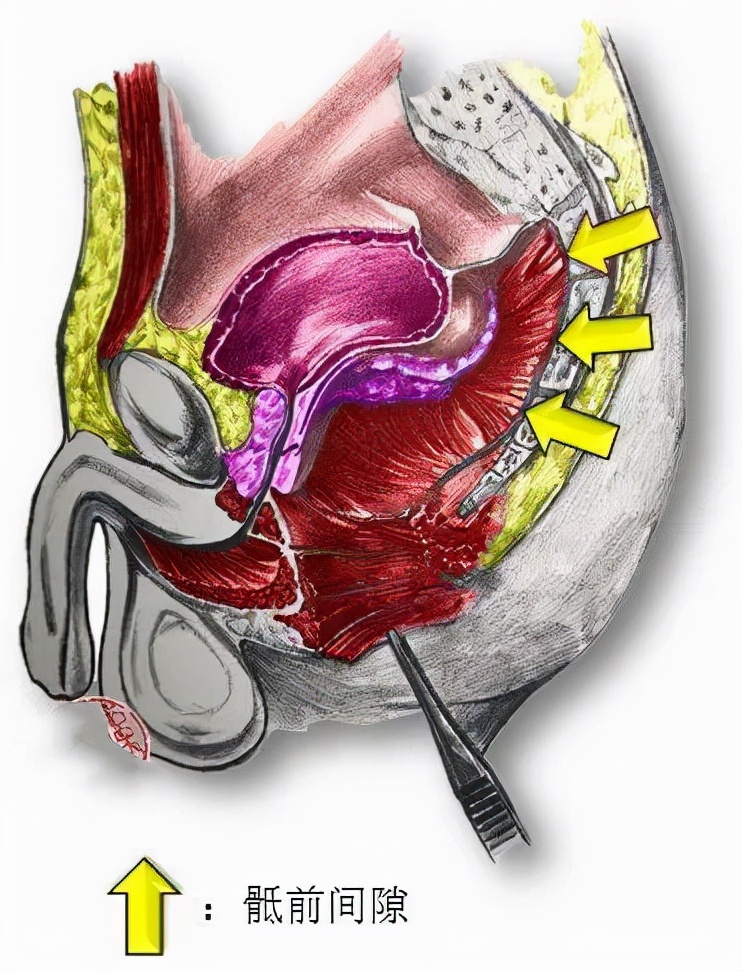

且骶前间隙是一个潜在的间隙, 周围比邻结构复杂 ,外科处理非常困难。

盆底的肌肉和直肠

大大增加手术难度